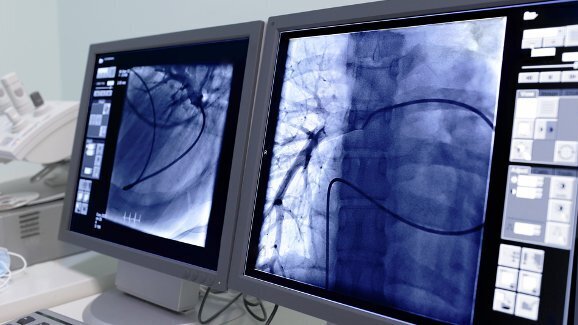

该研究小组分析了3587名属于高危人群的受调查者的数据,并对他们进行头颈部鳞状细胞癌的筛检。这三千余名调查者均属于年龄在五十周岁以上的吸烟人群。

从统计数据来看,每年在十万名美国人当中只有不到43人会被诊断出头颈部癌症。然而,在这批受调查人群当中,这个比率则高达71.4。其中大部分确诊的受调查者为男性,且烟龄较长,每日吸烟量比常人多。

根据研究小组所进行的有关肺癌筛检有效性的研究,他们推断,在这一高危人群当中实施头颈部鳞状细胞癌的筛检将可以降低患者的死亡率。

“头颈部癌症属于一种较为少见的癌症类别,因此,在普通人群中进行头颈部癌症的筛检并无太大的实用价值。”这项报告的合著者,匹茨堡大学医疗中心肺癌研究中心副主任David O. Wilson 博士介绍,“然而我们也发现,研究当中的肺癌易患人群,同时也很有可能通过头颈部癌症筛检而受益。因此,若这项筛检能够降低这一高危人群的死亡率,那么它也同时可以成为头颈部癌症早发现、早诊断的有效手段。”